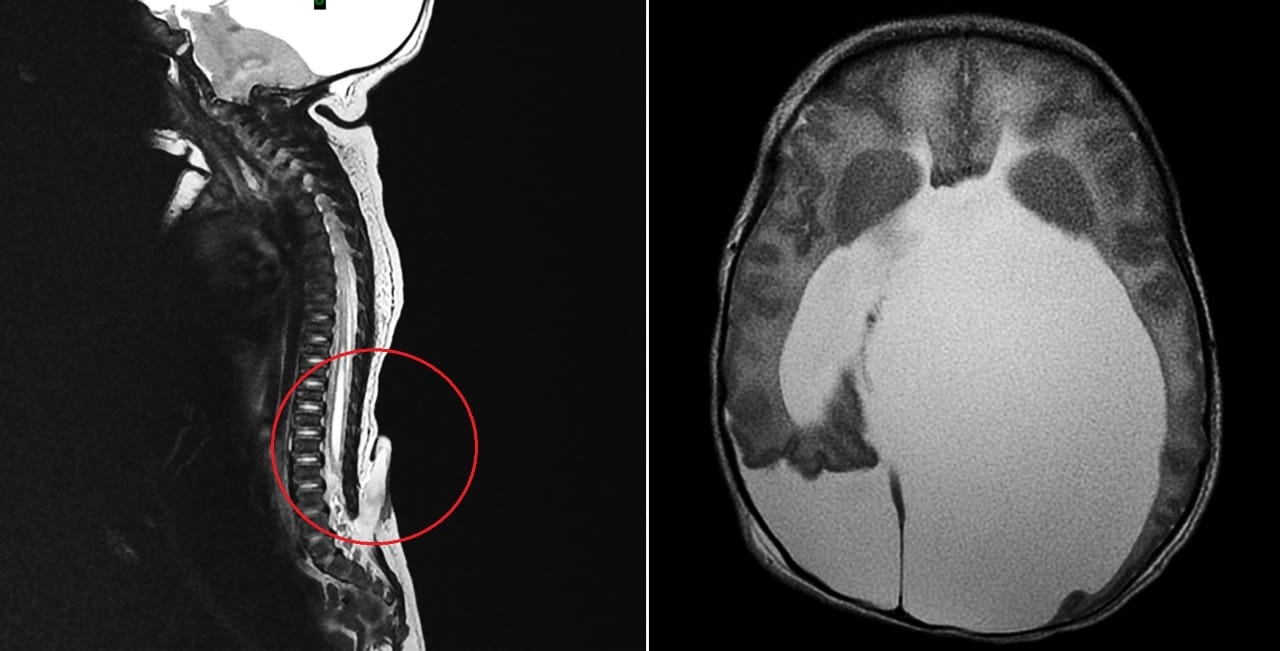

كما أشار الدكتور أبو ناضر إلى أن نتائج الصور الشعاعية والرنين المغناطيسي أظهرت أيضاً وجود تجمع للسوائل داخل الدماغ والنخاع الشوكي يعرف باسم (Hydrocephalus) تسبب في دفع منطقة المخيخ إلى الأسفل وأدى إلى حدوث ضغط شديد على النخاع، موضحاً أنه بعد العملية الأولى ببضعة أيام أجريت الجراحة الثانية وتم فيها إزالة المياه وتحويلها من بطينات الدماغ إلى البطن عبر قسطرة وجهاز متخصص ومتطور.

وقال الدكتور أبو ناضر بأن الجراحة الرابعة أجريت أيضاً وتم فيها تصحيح التشوه الخلقي والمعروف باسم (Arnold Chiari Malformation with Syringomyelia)، وذلك من خلال فتح الجمجمة من الخلف وتوسيع مكان المخيخ علاوة على تصحيح وتعديل مجرى مياه الدماغ والسماح لها للانتقال من المخيخ إلى البطن حتى تسير بطريقة طبيعية بعد إزالة الضغط على النخاع الشوكي.